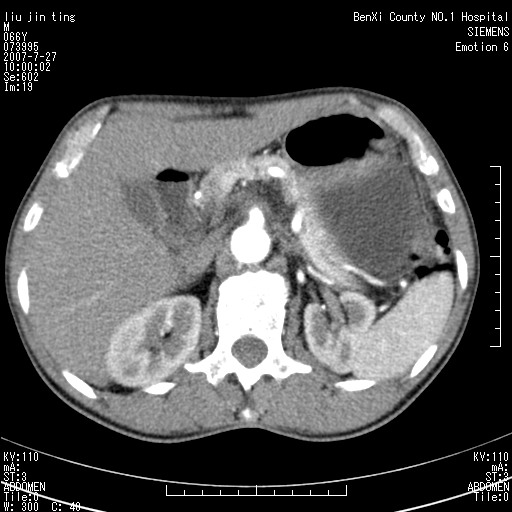

腹痛,背痛,无恶心呕吐,不黄,彩超示胰腺钩癌,ct扫描病灶平扫30-40hu,增强后动脉期40--60hu,静脉期50-68hu,真的是钩突上的么?您要试一试么?

动脉期

静脉期

沿着肠系膜上动脉呈匍匐性生长的软组织肿块,形态不规则,包绕肠系膜上动脉,呈明显强化,考虑来源于肠系膜的恶性肿瘤

沿着肠系膜上动脉呈匍匐性生长的软组织肿块,形态不规则,包绕肠系膜上动脉,呈轻-中度强化,考虑来源于肠系膜的恶性肿瘤。

钩突是正常的,只见腹膜后淋巴结的肿大,考虑淋巴瘤或转移可能。